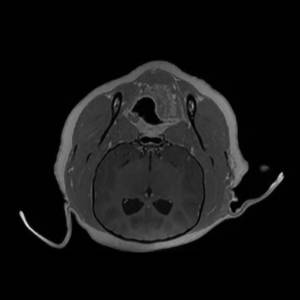

Main Gallery

Playing with a photo gallery function. It is possible to have multiple galleries, each within a namespace.